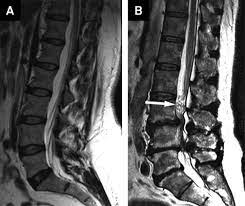

Signs and symptoms include low back pain, pain that radiates down the leg, numbness around the anus, and loss of bowel or bladder control. Anatomy of lower lumbar and sacral spine (lavy 2009). Mri of marked dural sac compression by surgical in the immediately postoperative period after uncomplicated lumbar laminectomy.// lumbar cauda equina syndrome associated with the use of gelfoam: Cauda equina syndrome (ces) is a condition that occurs when the bundle of nerves below the end of the spinal cord known as the cauda equina is damaged. The spinal cord ends at the lower level of t12 or l1 vertebrae. Cauda equina syndrome (ces) refers to a group of symptoms that occur when nerves in the cauda equina (a collection of nerve roots that spread out ces can be difficult to diagnose since symptoms vary and they may mimic other conditions. Cauda equina syndrome (ces) is a particularly serious type of nerve root problem. Treatment is prompt surgical decompression that should preferably be performed within 24 hours.

Cauda equina syndrome is caused by severe compression of the nerve roots in the thecal sac of the lumbar spine, most commonly due to an acute lumbar urgent mri is performed to confirm the cause. Cauda equina syndrome (ces) is a condition that occurs when the bundle of nerves below the end of the spinal cord known as the cauda equina is damaged. Mris are valuable in diagnosing the cause of cauda equina syndrome as. Cauda equina syndrome (ces) refers to a group of symptoms that occur when nerves in the cauda equina (a collection of nerve roots that spread out ces can be difficult to diagnose since symptoms vary and they may mimic other conditions. Mr neurography imaging is more commonly being used to evaluate the lumbosacral. Learn about diagnosis, including mri testing. Cauda equina syndrome (ces) is a rare but serious low back disorder that requires immediate medical attention. Tests that may be used to diagnose ces include mri, ct. Cauda equina syndrome may result from any lesion that compresses ce nerve roots. Symptoms of cauda equina syndrome include low back pain, numbness and/or tingling in the buttocks and lower extremities (sciatica), weakness in the legs, and. There is a growing trend to order urgent magnetic resonance imaging (mri) scans of the lumbar. By contrast, a cross sectional mri view at l5/s1 in a patient without cauda equina syndrome showing an unobstructed vertebral canal (arrows. 3 treating cauda equina syndrome.

2 receiving diagnostic tests and examinations. This is a rare disorder where there is pressure on the nerves. Sagittal mri of a patient with cauda equina syndrome secondary to a large lumbar disk herniation. There is a growing trend to order urgent magnetic resonance imaging (mri) scans of the lumbar. Cauda equina syndrome (ces) occurs when there is dysfunction of multiple lumbar and sacral nerve roots of the cauda equina.